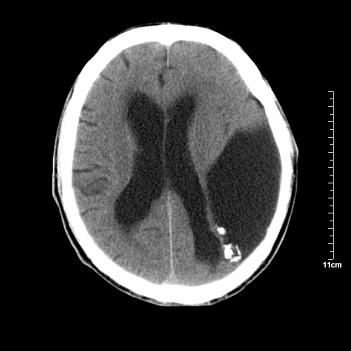

男性患者,72岁,近两天头晕来我院就诊。 因患者血压太高而未做增强,建议病人去市医院做mri检查。等得到mri随访结果再公布给大家。 测及左颞顶枕叶病灶ct值分别为5hu 30hu 729hu。

考虑左侧颞顶枕叶少突胶质细胞瘤。 今天随访患者手术病理结果 病理回报为胶质瘤2级 钙化

左侧颞顶枕叶巨大囊性病灶,灶内见小片实性区且灶内及灶周围大量团块状钙化影,灶周水肿少.左侧室枕角内见环形钙化,可见较清晰前壁,钙化与室壁似有间隙.

考虑1寄生虫病2表皮样囊肿钙化3血管畸形,其他不排

囊变明显,钙化明显,部分实性组织,轻度占位,左侧脑室受压---考虑 少突胶质细胞瘤,畸胎瘤,寄生虫病

今天追踪患者家属手术病理结果 病理回报为胶质瘤2级并钙化

病理回报为胶质瘤2级并钙化